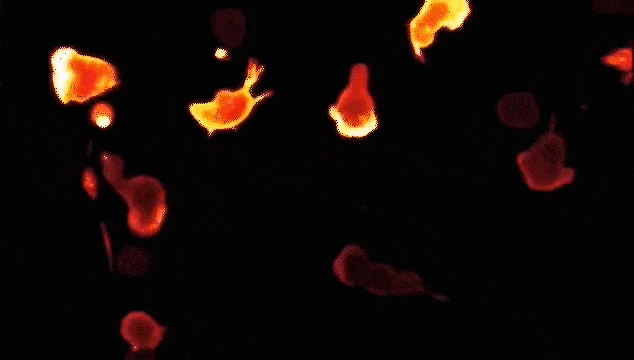

細胞藥物長啥樣?讓我們在顯微鏡中認識真正的“癌癥殺手”,來自德國的科學家將CAR-T細胞攻擊癌細胞的圖像放大了2000倍!

微觀鏡頭下的CAR-T對抗腫瘤細胞,想想都很過癮的斗爭大片!在高清的鏡頭下將CAR-T對抗癌細胞的“搏斗”場面展露無疑。讓我們先睹為快吧!

不僅乳腺癌,該掃描電子顯微鏡照片顯示CAR-T細胞(橙色)正在攻擊白血病細胞(紅色)。